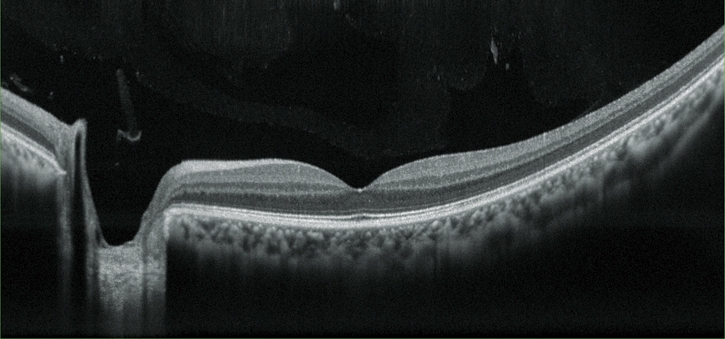

超高分辨率圖像

OCT成像時,平均提供多達(dá)50張圖像進(jìn)行疊加,可根據(jù)實際情況,選擇超精細(xì)、精細(xì)和普通OCT敏感度。RS-330內(nèi)置12兆像素CCD攝像頭,能夠提供高質(zhì)量眼底圖像。